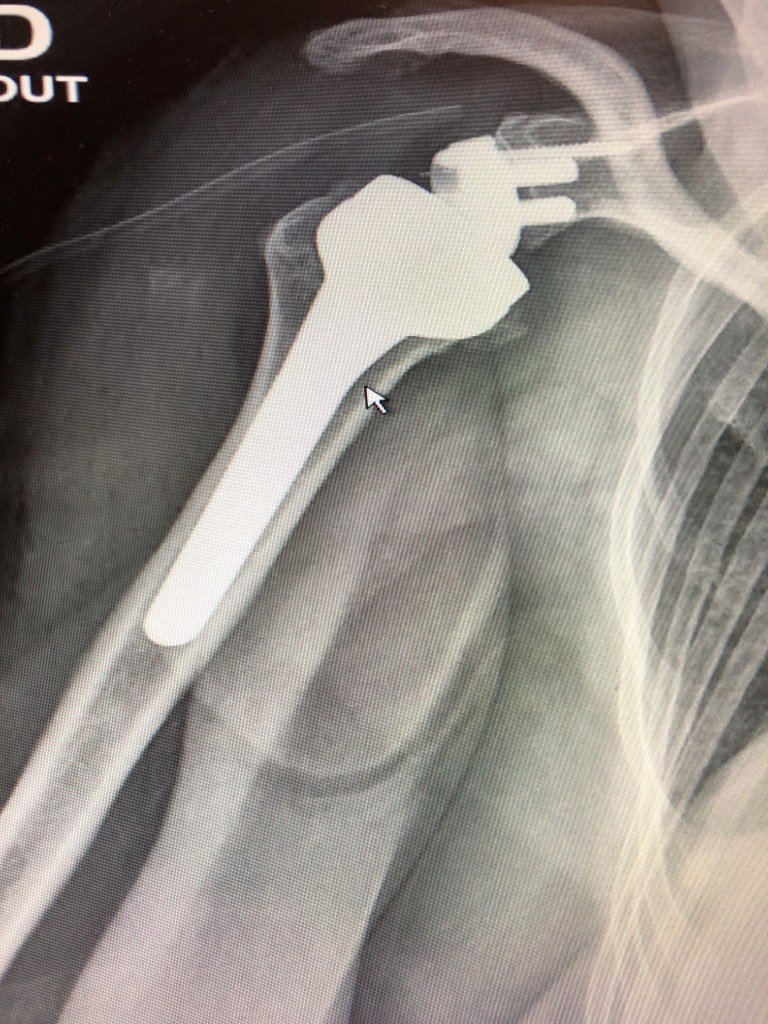

Vous trouverez ci après les interventions réalisées par le Dr DOLEAC